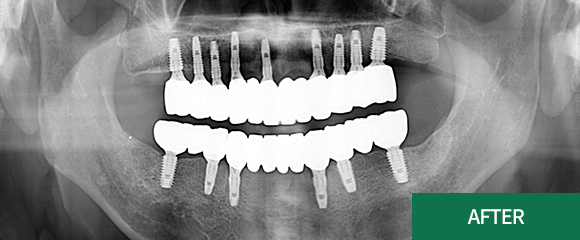

전악(전체) 임플란트

CASE 2